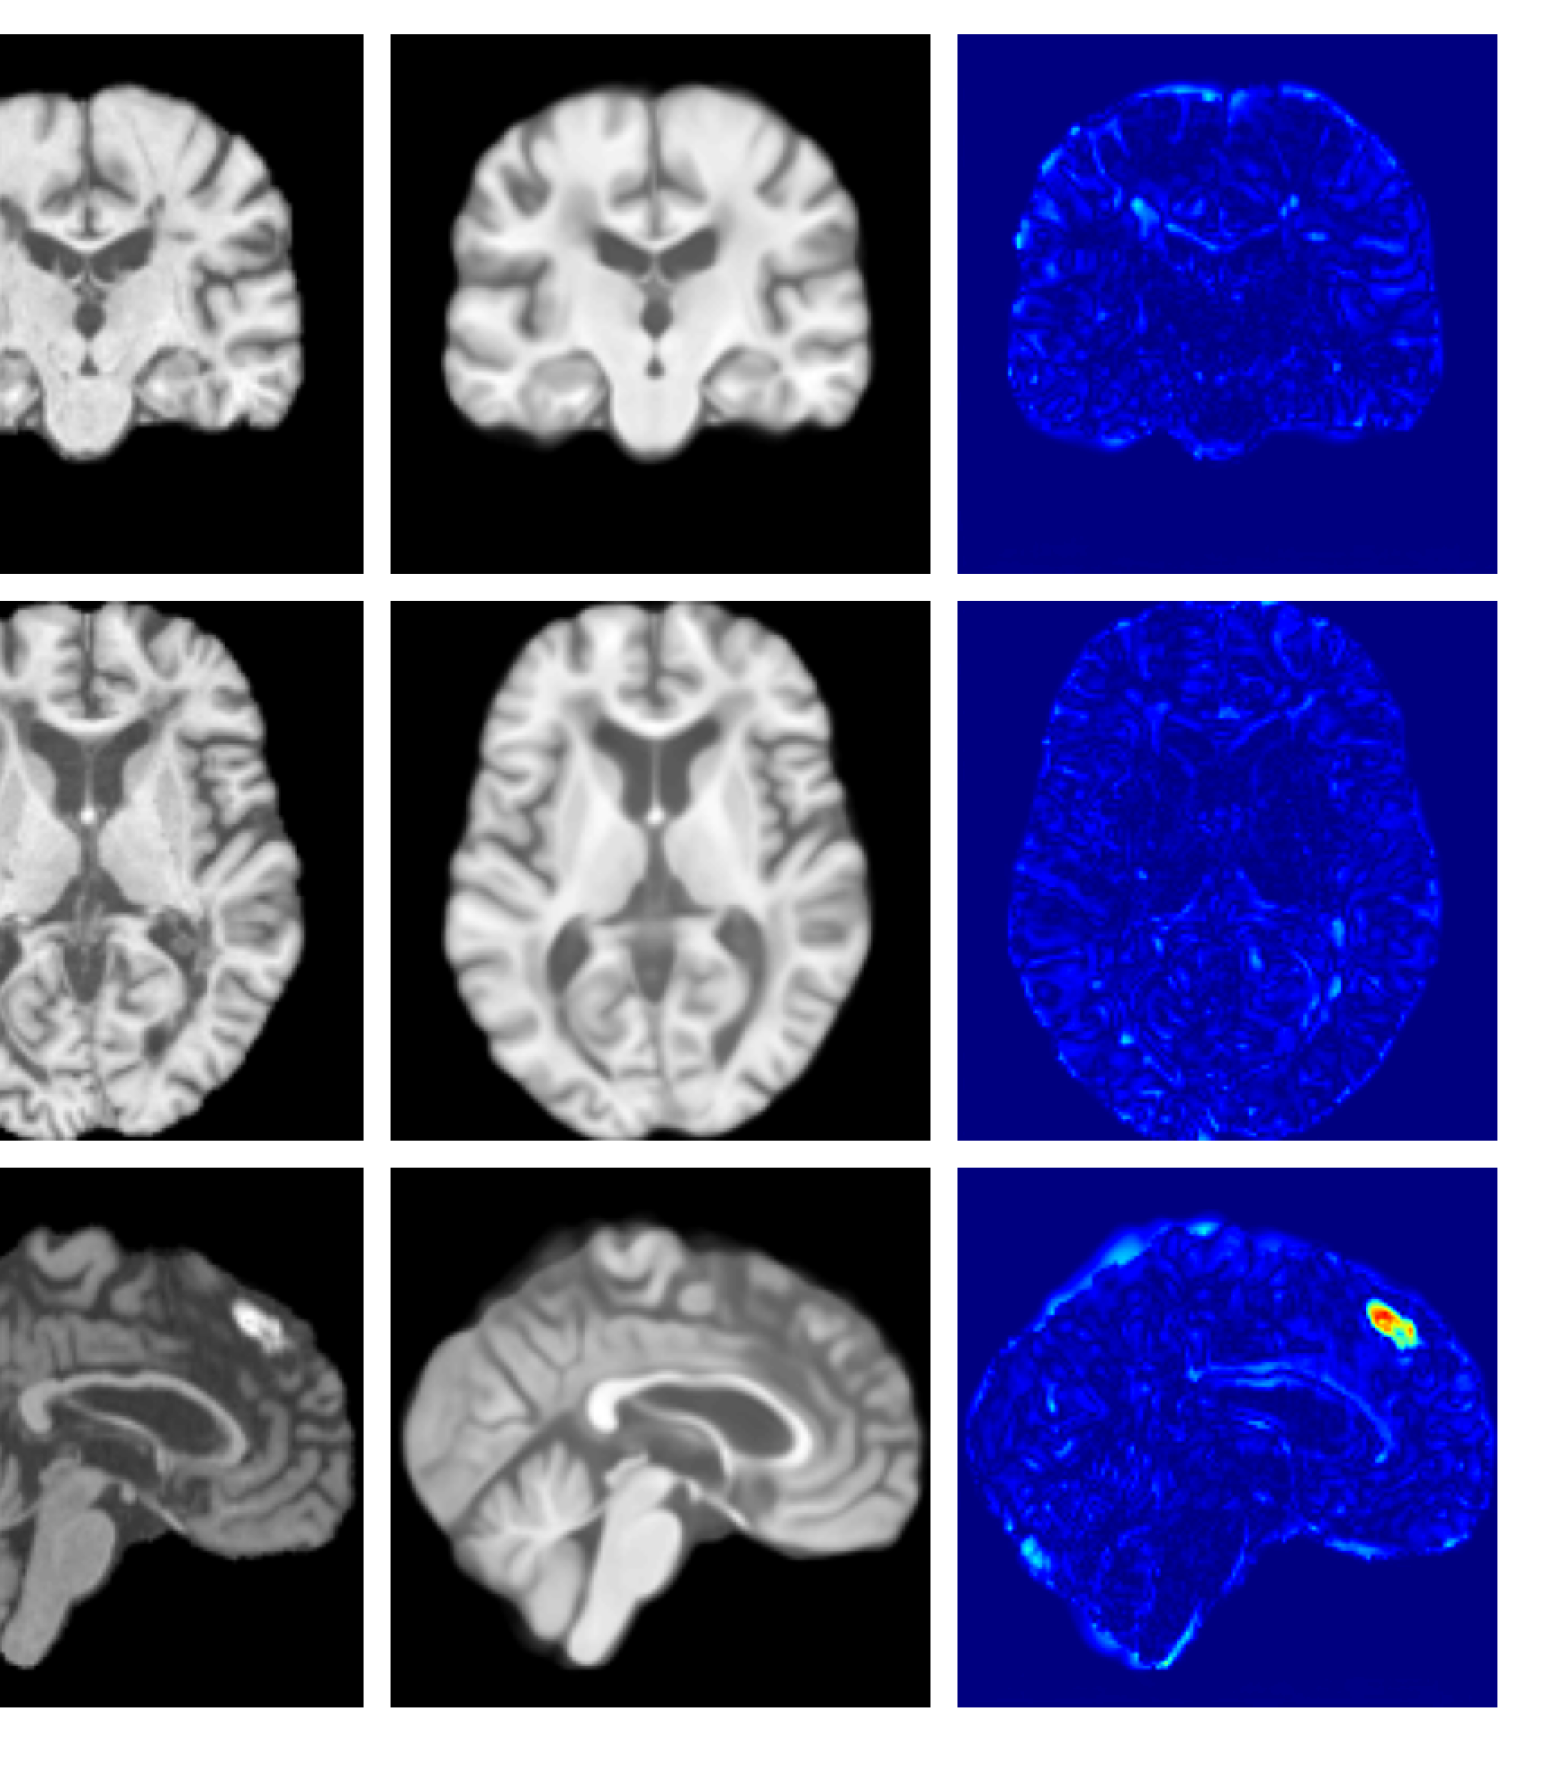

Figures 8 and 9 are enlarged versions of Figures 3 and 4 respectively, with the latter now including results from all compared methods. Figure 10 provides example reconstructions and anomaly maps for an AD subject from the ADNI disease cohort.

Figure 10: Example reconstructions and anomaly maps for an AD sample from the disease cohort of the ADNI dataset. We expect to see some inpainting of atrophied tissue whilst retaining the defining characteristics of the individual sample.